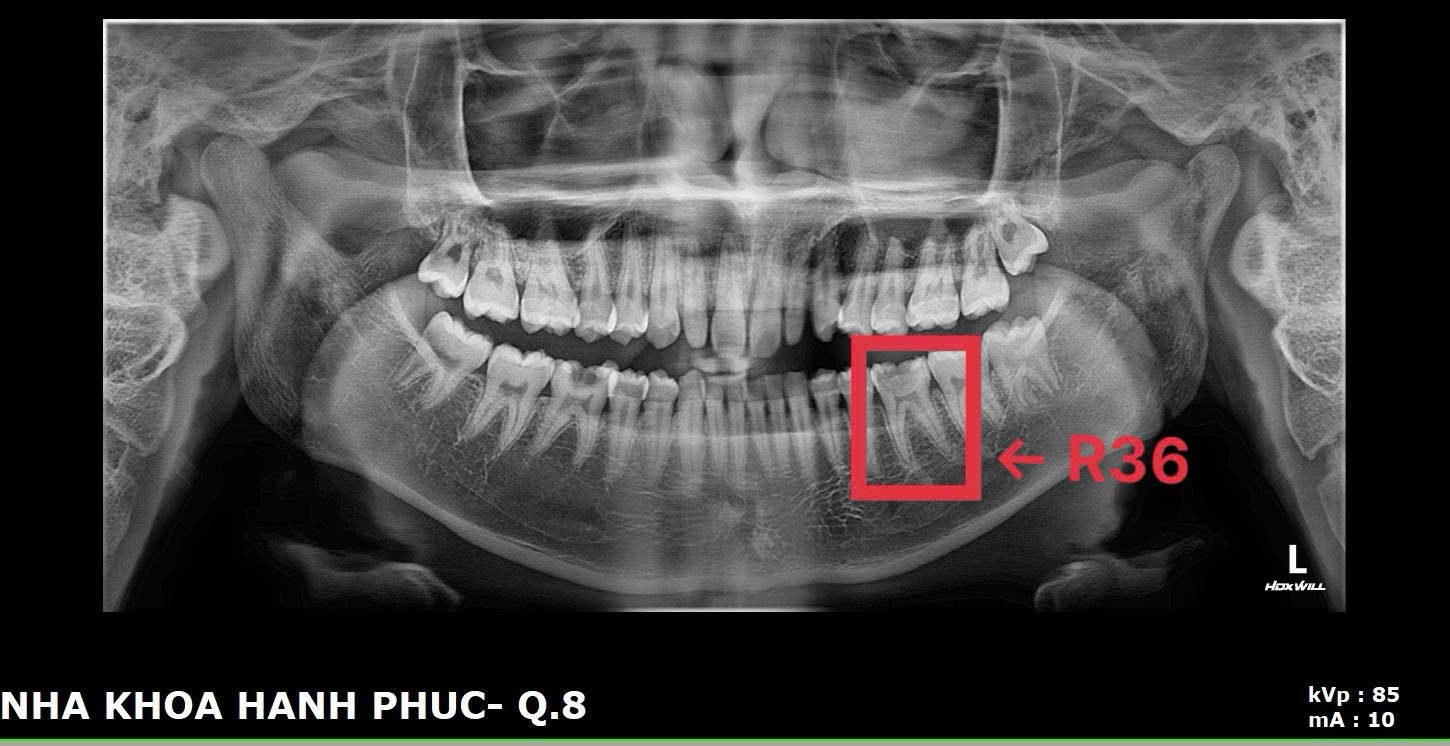

Bệnh nhân D.H.P.T. (17 tuổi) đến khám trong tình trạng đau nhức răng. Kết quả thăm khám và chụp X-quang cho thấy hai răng hàm lớn (R36 và R46) bị sâu nặng, tổn thương sát tủy.

Ban đầu, bệnh nhân chỉ mong muốn nhổ bỏ răng để chấm dứt đau nhức. Tuy nhiên, BS.CK1 Phan Bá Ngọc - Giám đốc phòng khám giải thích rằng, việc nhổ răng hay lấy tủy sẽ ảnh hưởng đến khả năng ăn nhai về lâu dài, đặc biệt với người trẻ tuổi. Sau khi tư vấn kỹ và thuyết phục, gia đình đồng ý để bác sĩ tiến hành phương pháp che tủy bằng vật liệu sinh học thế hệ mới.

Sau 2 tháng điều trị, BS.CK1 Phan Bá Ngọc cho biết tình trạng bệnh nhân đã hết đau nhức, ăn nhai bình thường, kết quả kiểm tra cho thấy tủy vẫn sống khỏe mạnh.